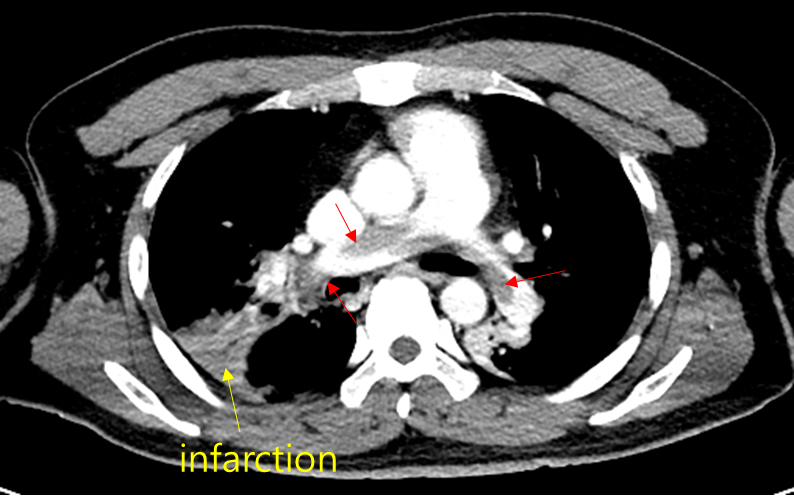

Img | CXR: Poor inspiration, r/o consolidation in Rt. upper lung field CT: Pulmonary a. thrombosis, r/o lung infarction in Rt. lung |

• PTE의 진단을 위해 빠르게 CXR 및 CT를 촬영했고, CT상 pulmonary a. 내부의 thrombus가 관찰되므로 PTE로 진단할 수 있다. 우측 폐에 wedge-shaped consolidation이 있는데, 이는 PTE의 microthrombus에 의해 흔히 발생하는 segmental lung infarction으로 추정된다. 객혈도 이 infarcted lung에 의해 발생했을 가능성이 높으며, 신체진찰상 우측 윗가슴의 호흡음 감소와도 correlation 된다.